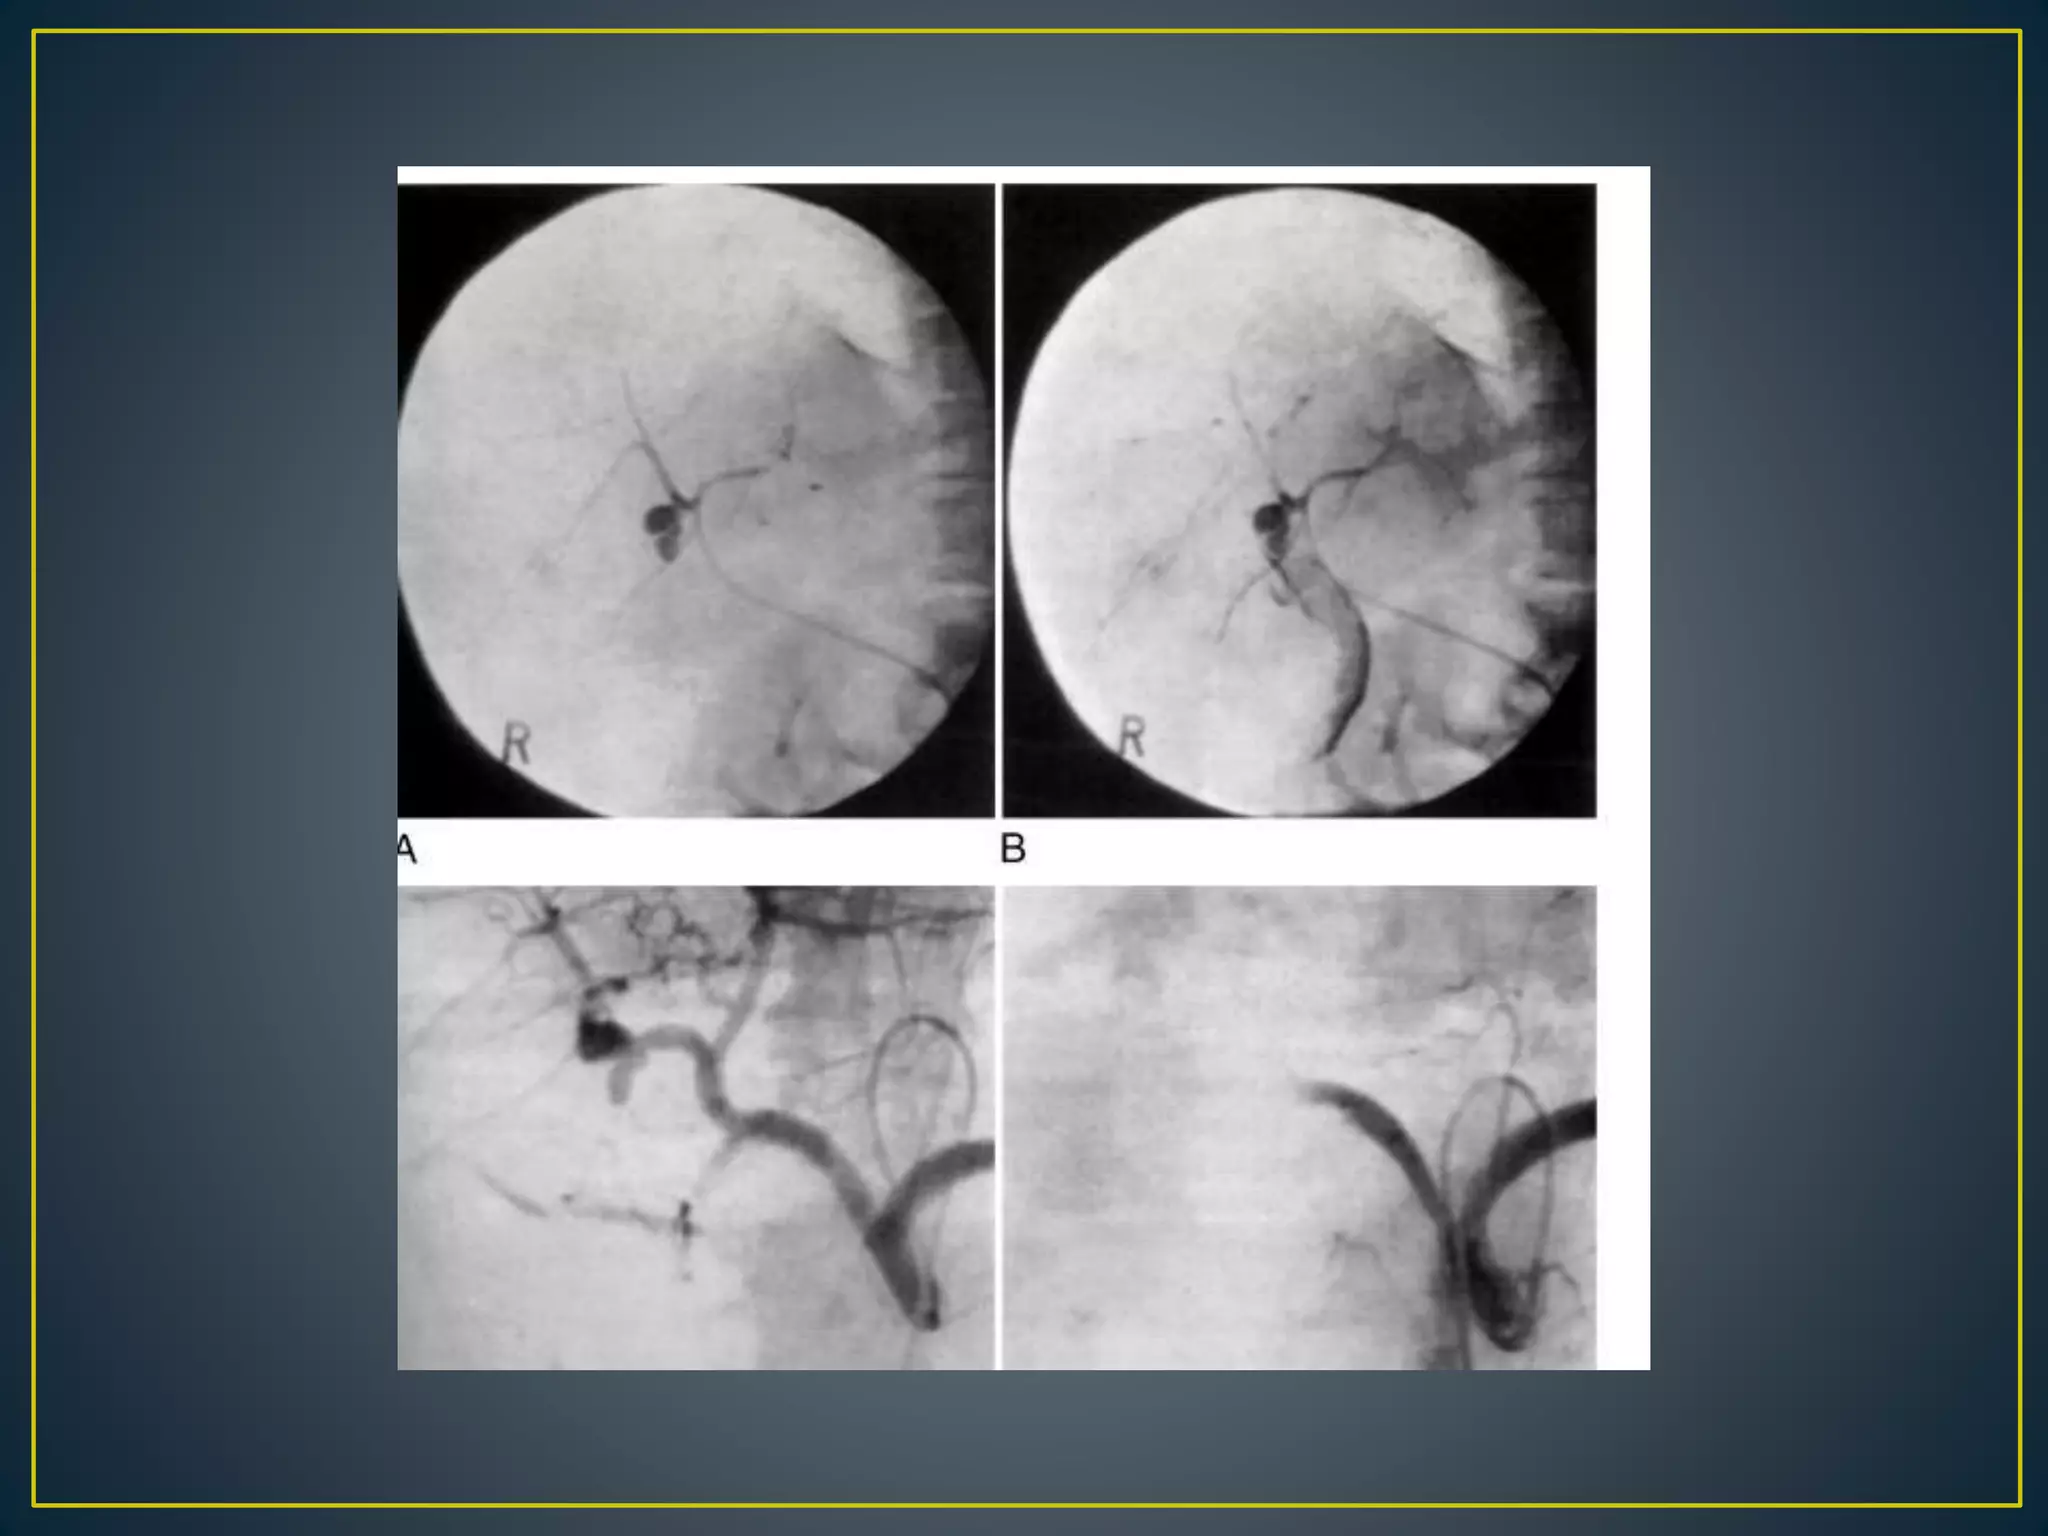

• Contrast media injection to blood vessel supply

of suspected organ of active bleeding .

- Active bleeding durling contrast media injection

> 0.5 ml/min.

• - Contrast media extravasation .

- Intensive blush of stomach :

Diffuse hemorrhagic gastritis .

- Esophageal or gastric varice in venous phase .

• Upper gastrointestinal bleeding is evaluated by celiac

arteriography, followed by superior mesenteric

arteriography

• If no bleeding site is found, selective left gastric or

gastro-duodenal arteriography(since it is most common

source of bleeding in gastric ulcer) may detect a subtle

bleed. If results of all these studies are negative,

inferior mesenteric arteriography should be

considered.

• Presumed lower gastrointestinal bleeding is evaluated

by superior mesenteric arteriography, followed by

inferior mesenteric arteriography.

• The hallmark of gastrointestinal hemorrhage is extrava-

sation of contrast material into the bowel

• Occasionally, extravasated contrast has a curvilinear

shape that mimics a vascular structure (pseudovein sign)